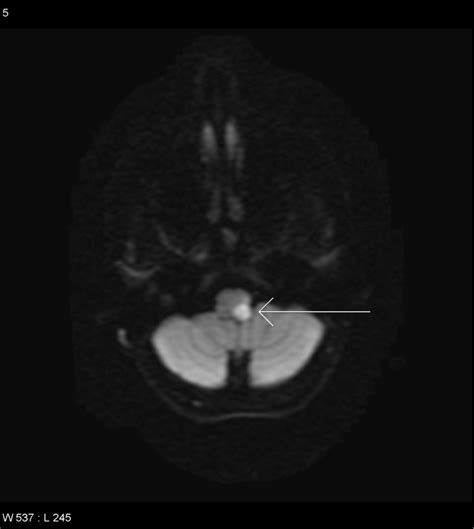

To confirm a Lateral Medullary Stroke, physicians rely on advanced imaging techniques. While a CT scan is often the first line of defense to rule out hemorrhage, it is frequently insensitive to small strokes in the brainstem. Therefore, a diffusion-weighted MRI (DWI-MRI) is the gold standard for visualization.